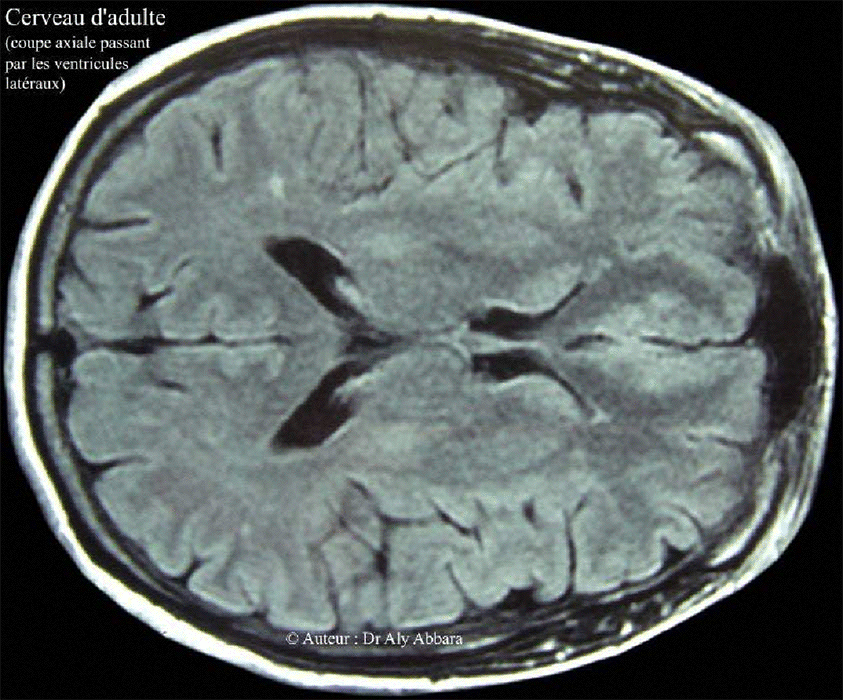

Cerveau d'adulte - IRM - Coupe axiale - ventricules latéraux

Cerveau d'adulte - coupe axiale passant par les cornes frontales

et occipitales des ventricules latéraux du cerveau

Image d'IRM